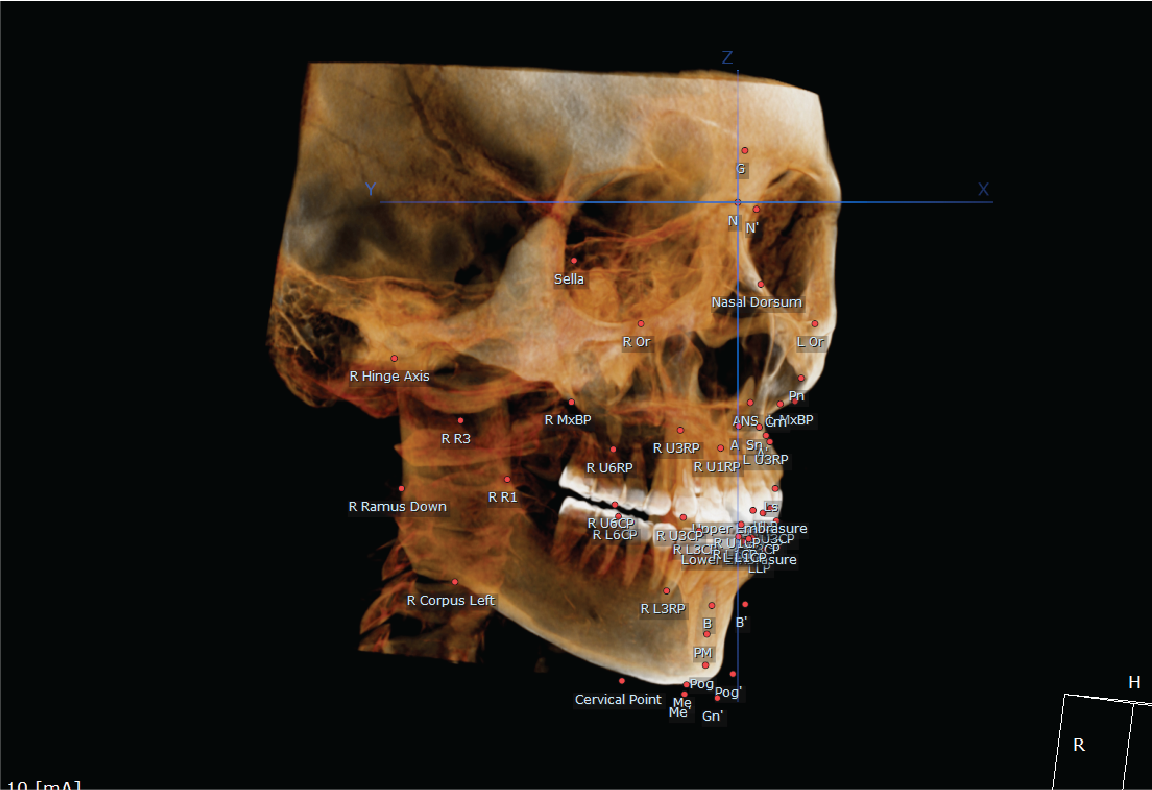

The Dentri MAX is the flagship model from HDX WILL, with the largest avail max FOV at 18x16.5, suitable for a wide scope of uses including advanced implantology, endodontics, orthodontics, orthognathic, bilateral TMJ & airway studies.

- 3D Ceph Acquisition & Analysis Module Included